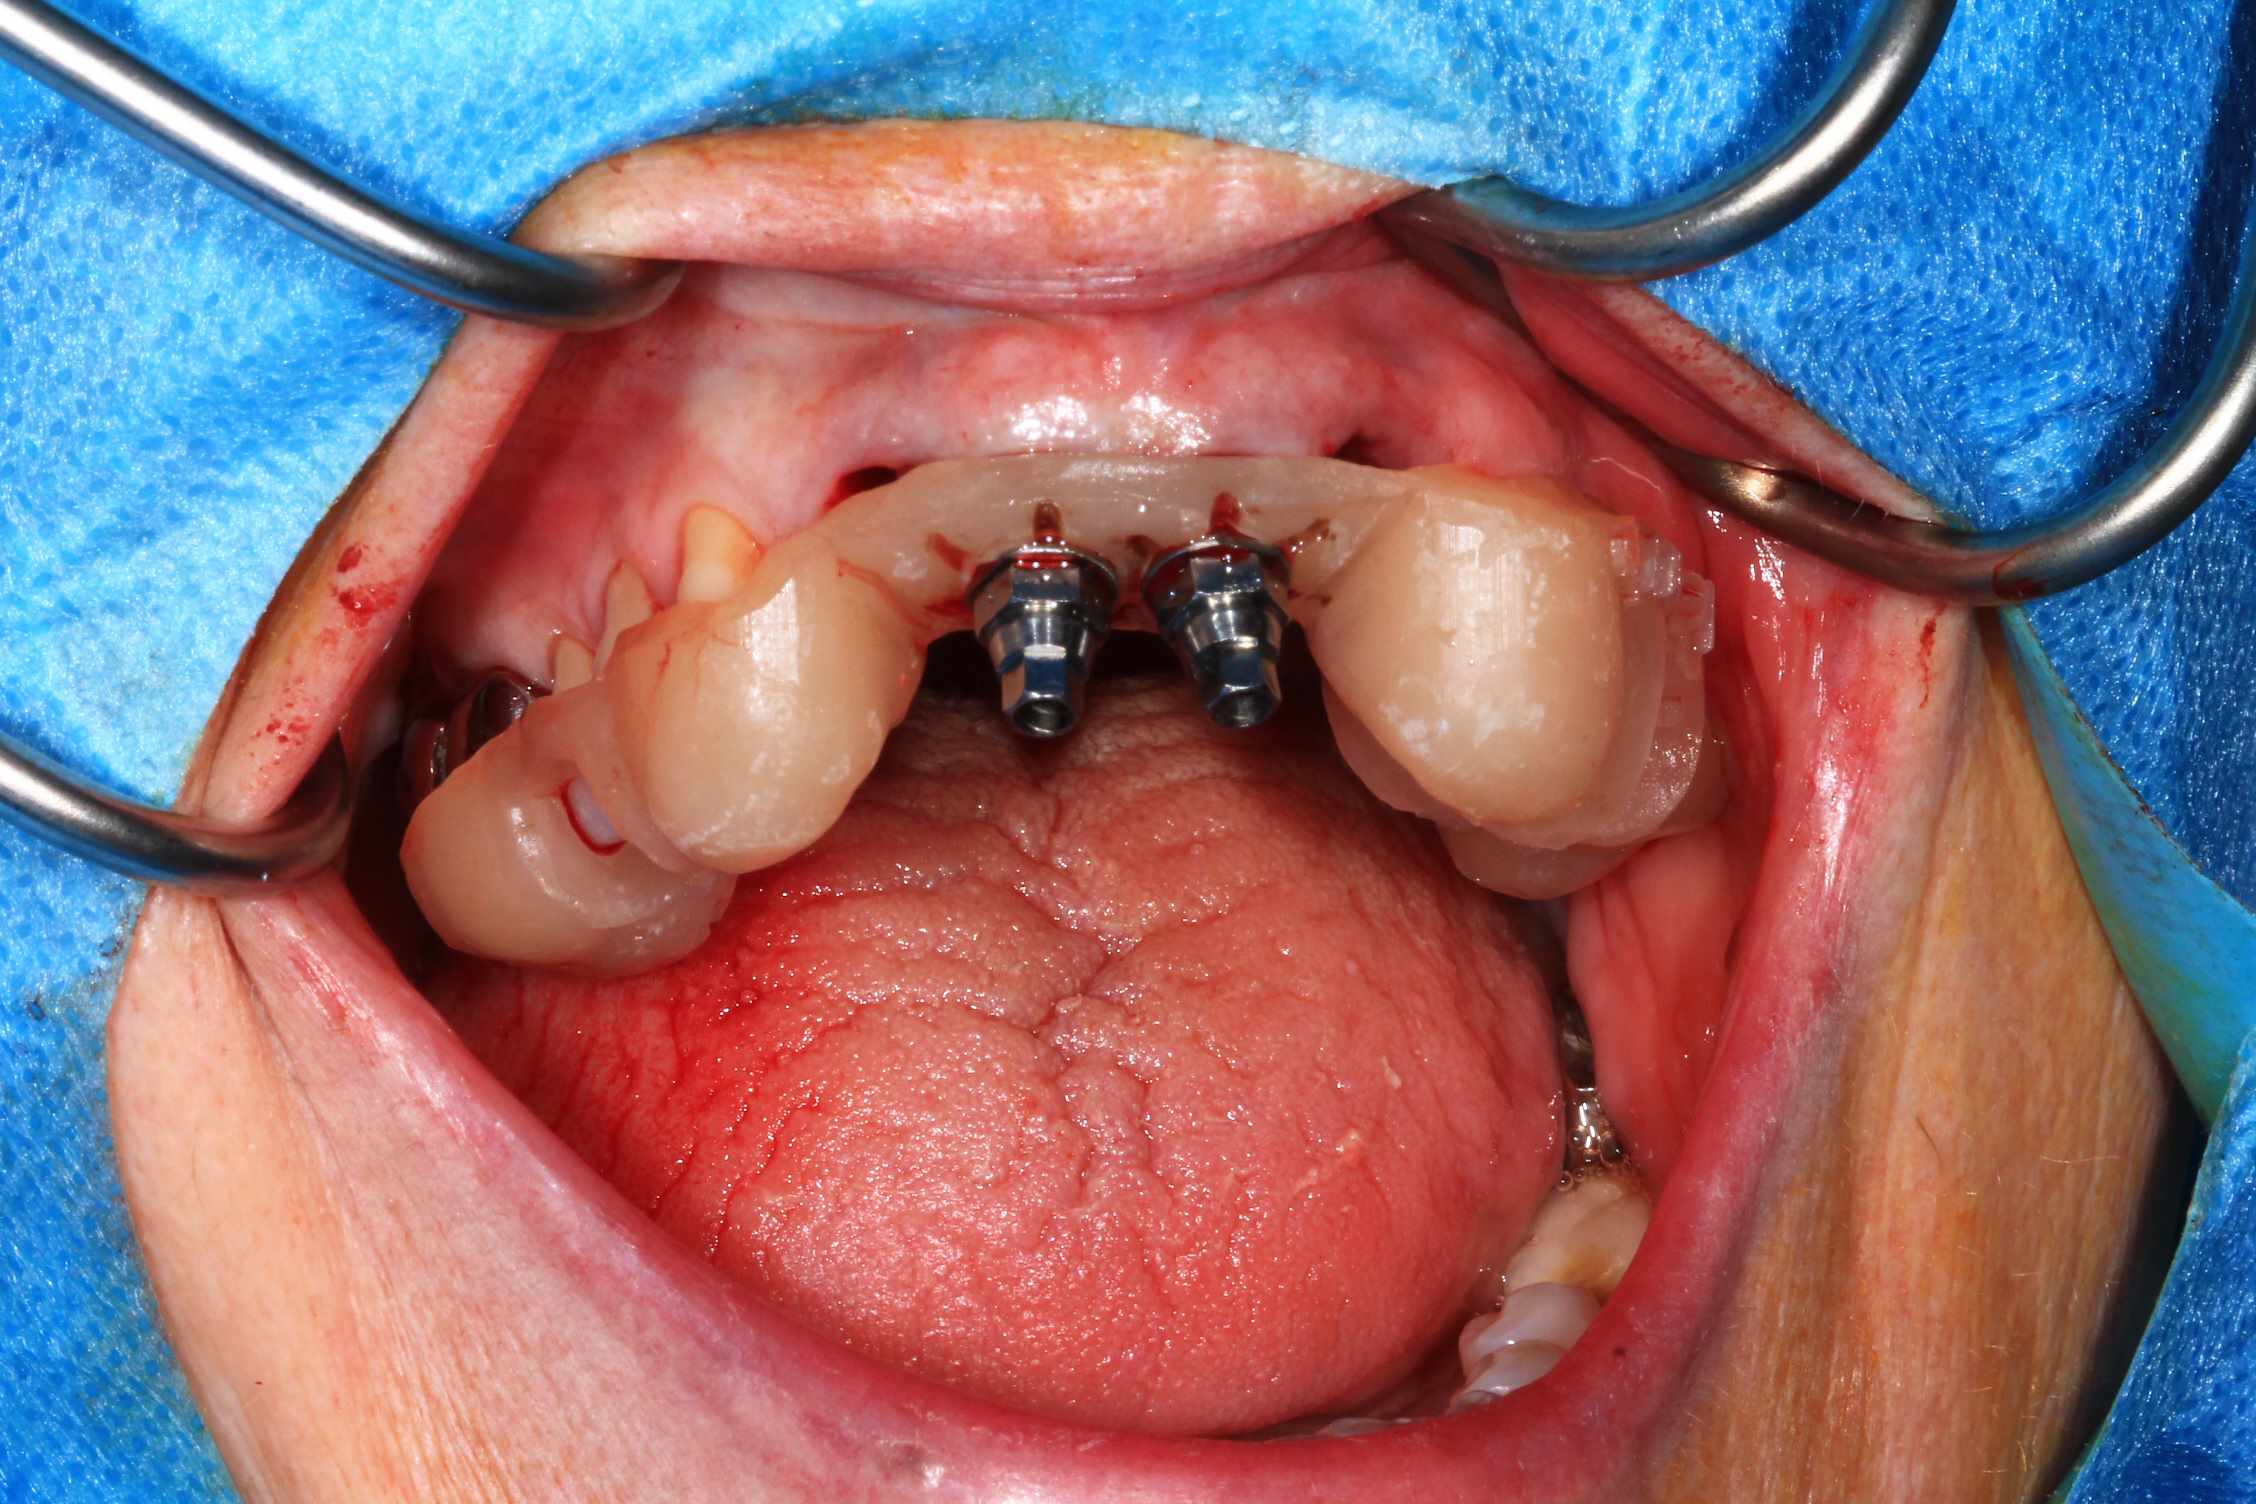

Chir : extraction, implant flapless et pose du bridge imprimé Flexera rosenscrew.

Oo2hlrfz7899rhfapzhptk1dqg77 - Eugenol

57n0uy1188a85maq093dyeqfkqlh - Eugenol

Ujfw7wykxh3fhbwxszqf740ci3rt - Eugenol

S7tplsv5ffydeo8n22bhttsnmndc - Eugenol